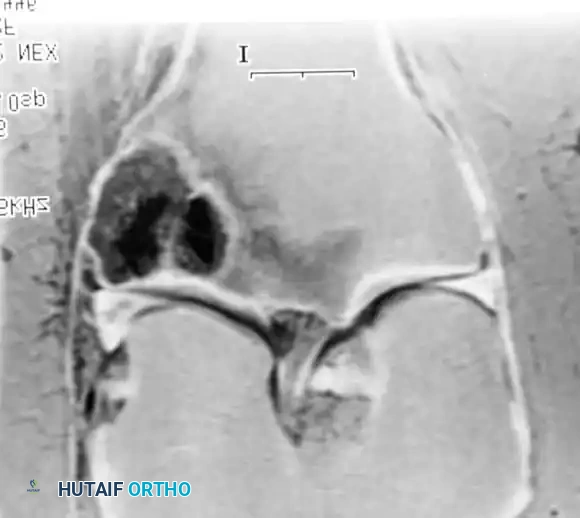

Fig. 22-19: (A) Anteroposterior view of the left hip of a 50-year-old woman with a history of breast cancer, disease-free for 2 years. A lytic lesion is seen in the femoral neck. Although the most likely diagnosis is metastatic carcinoma, a biopsy must be performed. This lesion proved to be a malignant fibrous histiocytoma (primary sarcoma). (B) Anteroposterior view after wide resection and endoprosthetic reconstruction. Prophylactic fixation of this presumed metastasis would have severely compromised her oncologic outcome.